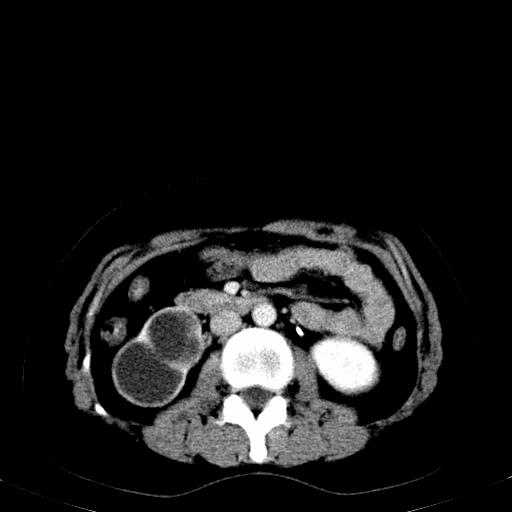

患者体检发现右肾体积增大,怀疑右肾积水

右肾多发囊肿,左肾、左输尿管结石

右肾重度积水,以肾盏积水明显,有分隔,上段输尿管轻度扩张,管壁增厚,考虑肾结核可能,请结合尿检查,胸部拍片排除肺结核。

右侧肾积水、左侧肾结石

右侧肾积水、左侧肾结石  ,要排除右肾结核可能。

右肾重度积水,建议ct向下扫描或逆行造影,左肾及左输尿管结石 .

1)不排除右肾结核可能。2)左肾及左输尿管上段结石?